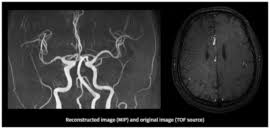

- MRA (자기공명혈관조영술): MRI 원리를 적용해 **혈관 내부 구조와 혈류 흐름**을 3D 영상으로 확인하는 검사입니다. 동맥류, 혈관 협착·폐쇄·혈전 등의 진단에 사용됩니다 :contentReference[oaicite:2]{index=2}.

- MRA는 혈관 가시화를 위해 **주로 조영제(가돌리늄 계열)**를 사용하지만, **비조영 투영기법**(Time-of-Flight, Phase Contrast 등)도 많습니다 :contentReference[oaicite:4]{index=4}.